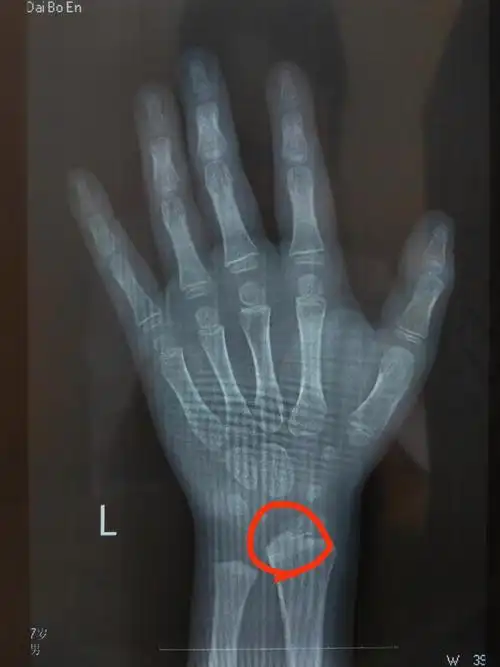

年龄只有看骨龄才能确定孩子现在的发育状态只有看骨龄才能知道孩子